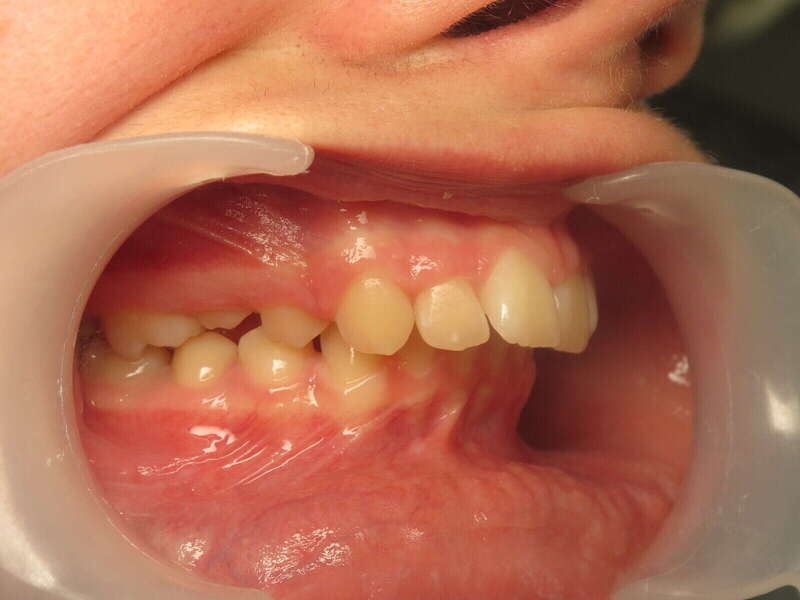

Cas n°1 traité par aligneurs (interception) - enfant

Ce cas d’interception chez un enfant de 8 ans démontre l'efficacité des aligneurs pour corriger des troubles fonctionnels précoces. Le diagnostic présentait des inversions d'articulé provoquant une déviation de la mandibule vers la gauche et un décalage des milieux.

Grâce à une coopération exemplaire et un traitement totalement indolore, l'expansion de l'arcade a permis de recentrer la mâchoire. Cette intervention a littéralement remis la croissance sur les rails, neutralisant le risque d'asymétrie faciale squelettique.

Résultats clés :

• Correction fonctionnelle : Recentrage immédiat de la mandibule et des milieux inter-incisifs.

• Prévention : Création d'un environnement favorable pour les dents définitives à venir.

• Bien-être : Approche douce respectant le confort de l'enfant.

C'est une étape fondamentale qui simplifie l'avenir orthodontique du patient tout en garantissant un développement facial harmonieux.